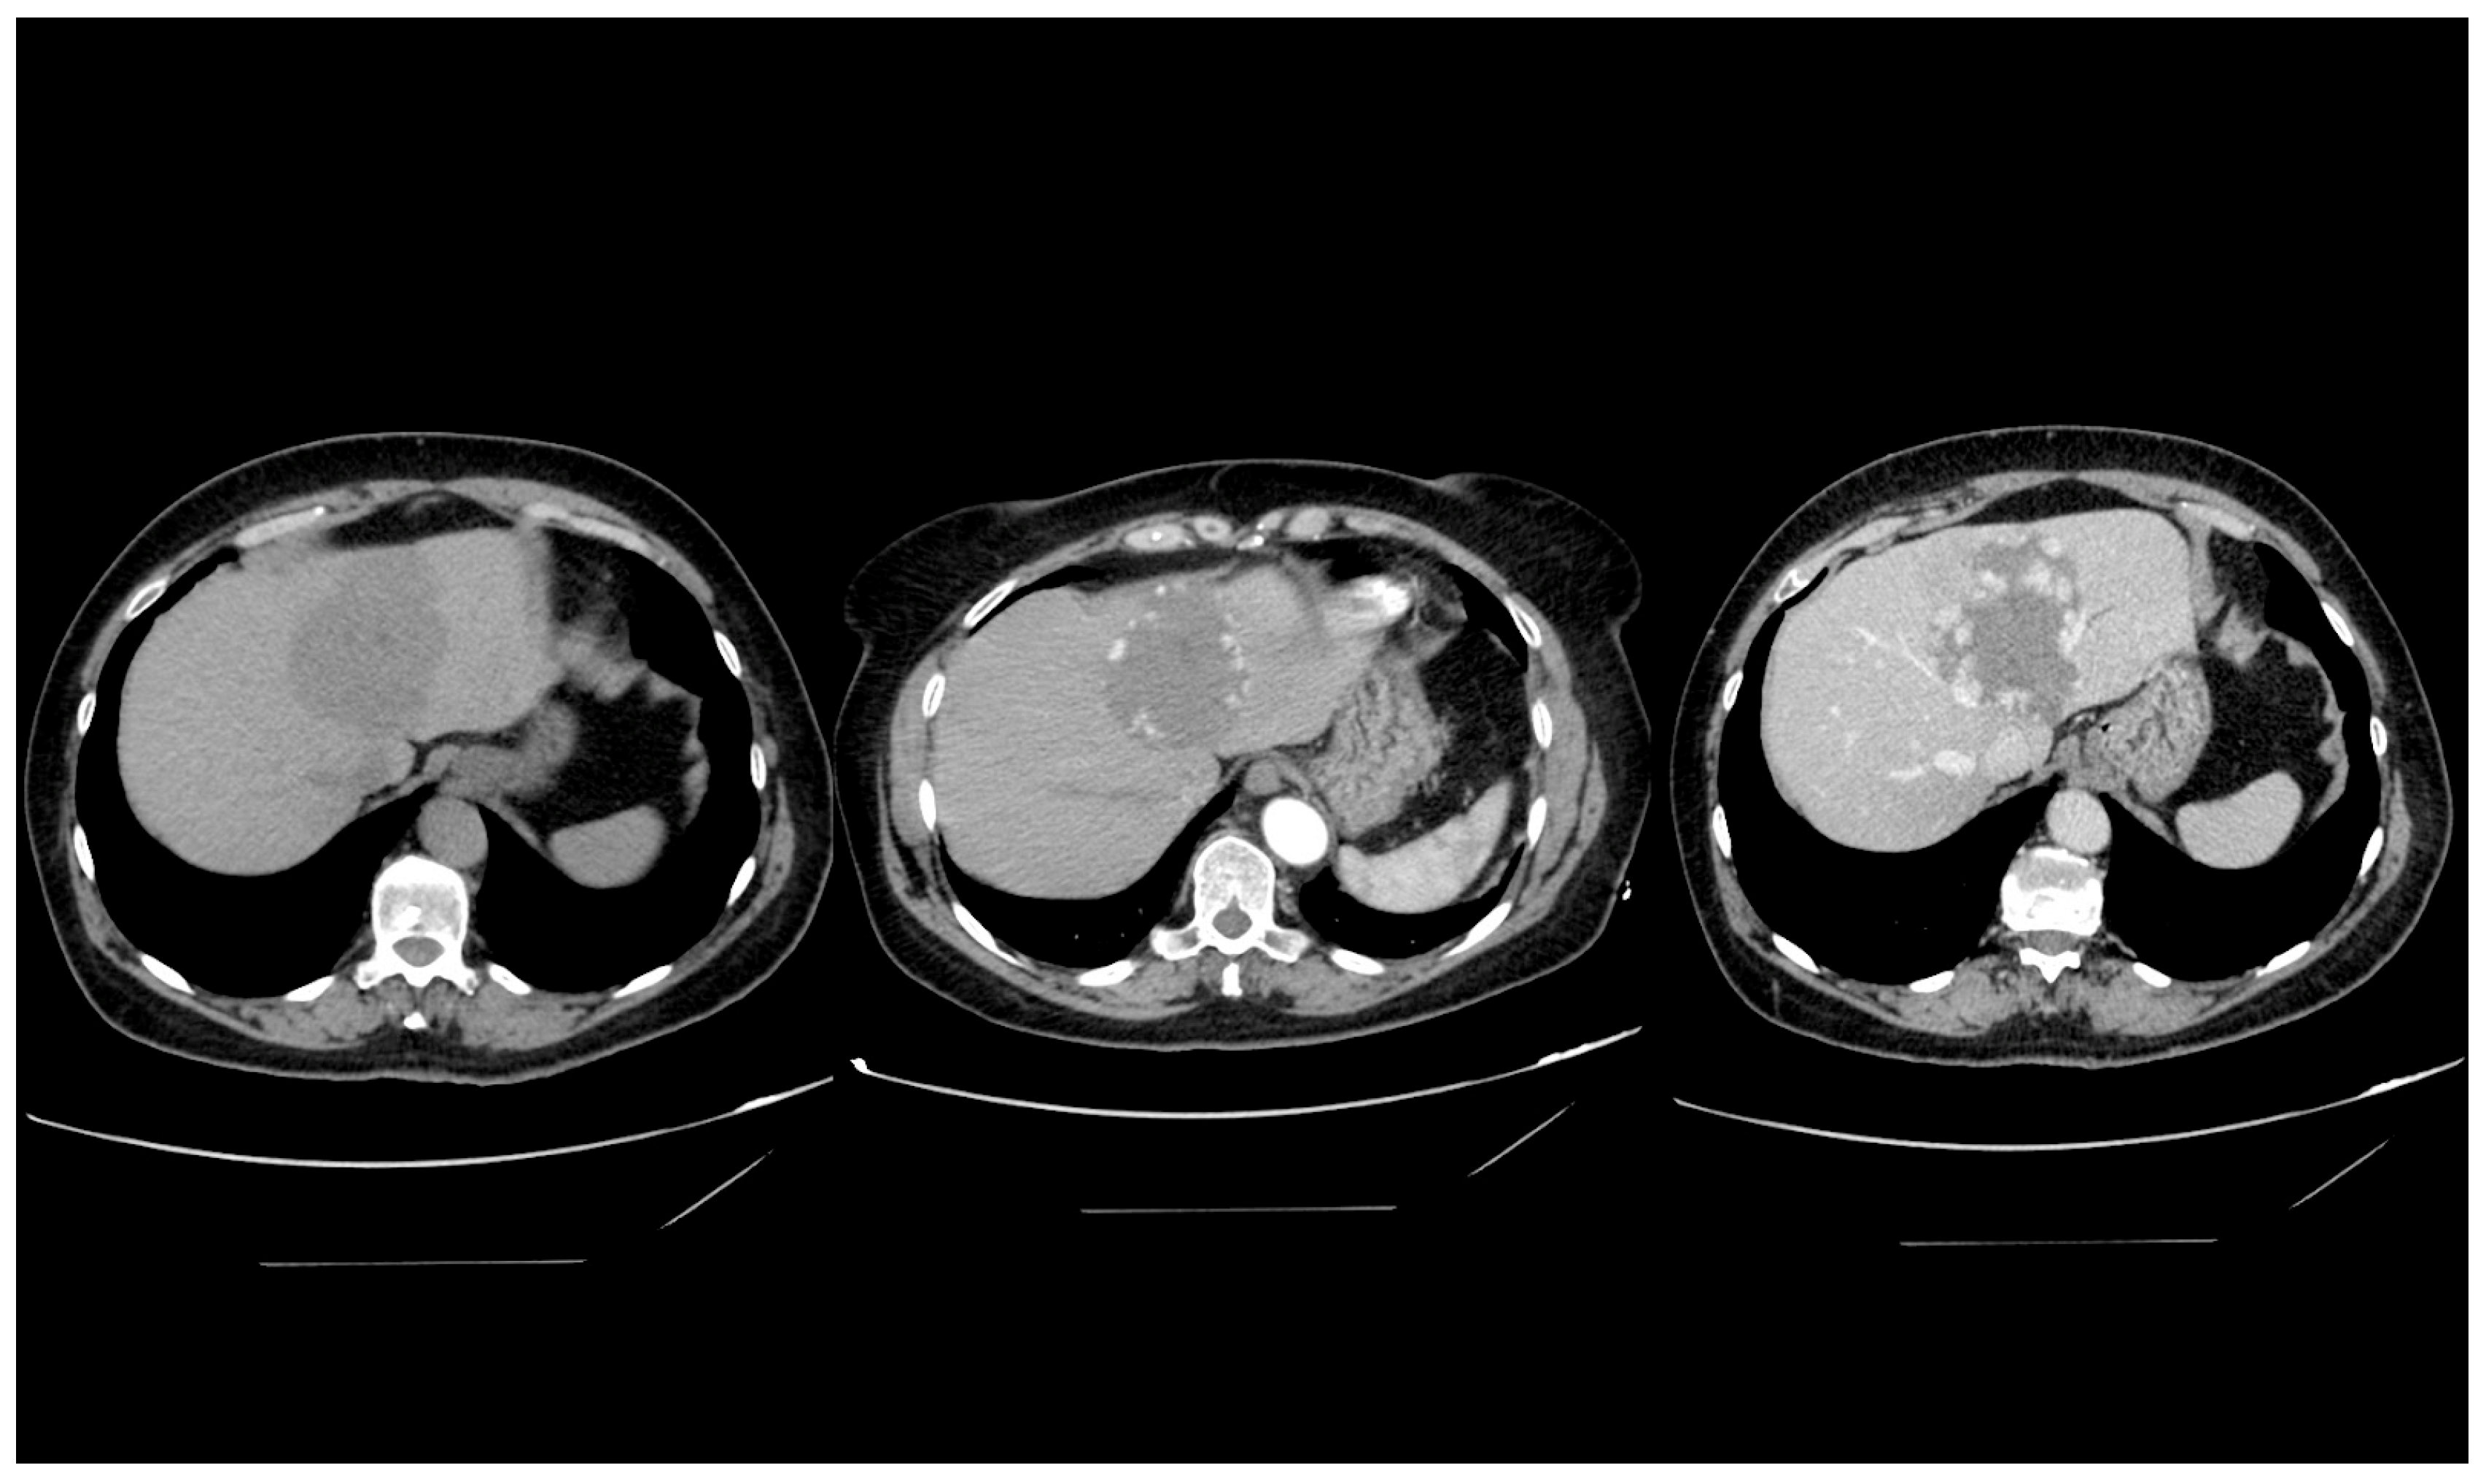

4.4. Computed Tomography

- Klotz, T.; Montoriol, P.F.; Da Ines, D.; Petitcolin, V.; Joubert-Zakeyh, J.; Garcier, J.M. Hepatic haemangioma: Common and uncommon imaging features. Diagn. Interv. Imaging 2013, 94, 849–859. [Google Scholar] [CrossRef] [PubMed]

- Mamone, G.; Di Piazza, A.; Carollo, V.; Cannataci, C.; Cortis, K.; Bartolotta, T.V.; Miraglia, R. Imaging of hepatic hemangioma: From A to Z. Abdom. Radiol. 2020, 45, 672–691. [Google Scholar] [CrossRef] [PubMed]

- Caseiro-Alves, F.; Brito, J.; Araujo, A.E.; Belo-Soares, P.; Rodrigues, H.; Cipriano, A.; Sousa, D.; Mathieu, D. Liver haemangioma: Common and uncommon findings and how to improve the differential diagnosis. Eur. Radiol. 2007, 17, 1544–1554. [Google Scholar] [CrossRef] [PubMed]

- Valls, C.; Reñe, M.; Gil, M.; Sanchez, A.; Narvaez, J.A.; Hidalgo, F. Giant cavernous hemangioma of the liver: Atypical CT and MR findings. Eur. Radiol. 1996, 6, 448–450. [Google Scholar] [CrossRef]

- Choi, B.I.; Han, M.C.; Park, J.H.; Kim, S.H.; Han, M.H.; Kim, C.W. Giant cavernous hemangioma of the liver: CT and MR imaging in 10 cases. Am. J. Roentgenol. 1989, 152, 1221–1226. [Google Scholar] [CrossRef]